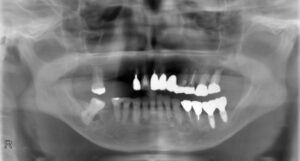

上顎前歯4本下顎臼歯7本症例

BEFORE AFTER 49歳男性/上下11本欠損/インプラント埋込手術 【治療内容】 上顎4本は虫歯が進行していてほ…